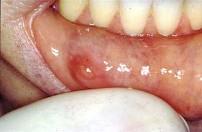

以下涎腺肿瘤最易发生种植复发的肿瘤是 ( )

C多形性腺瘤